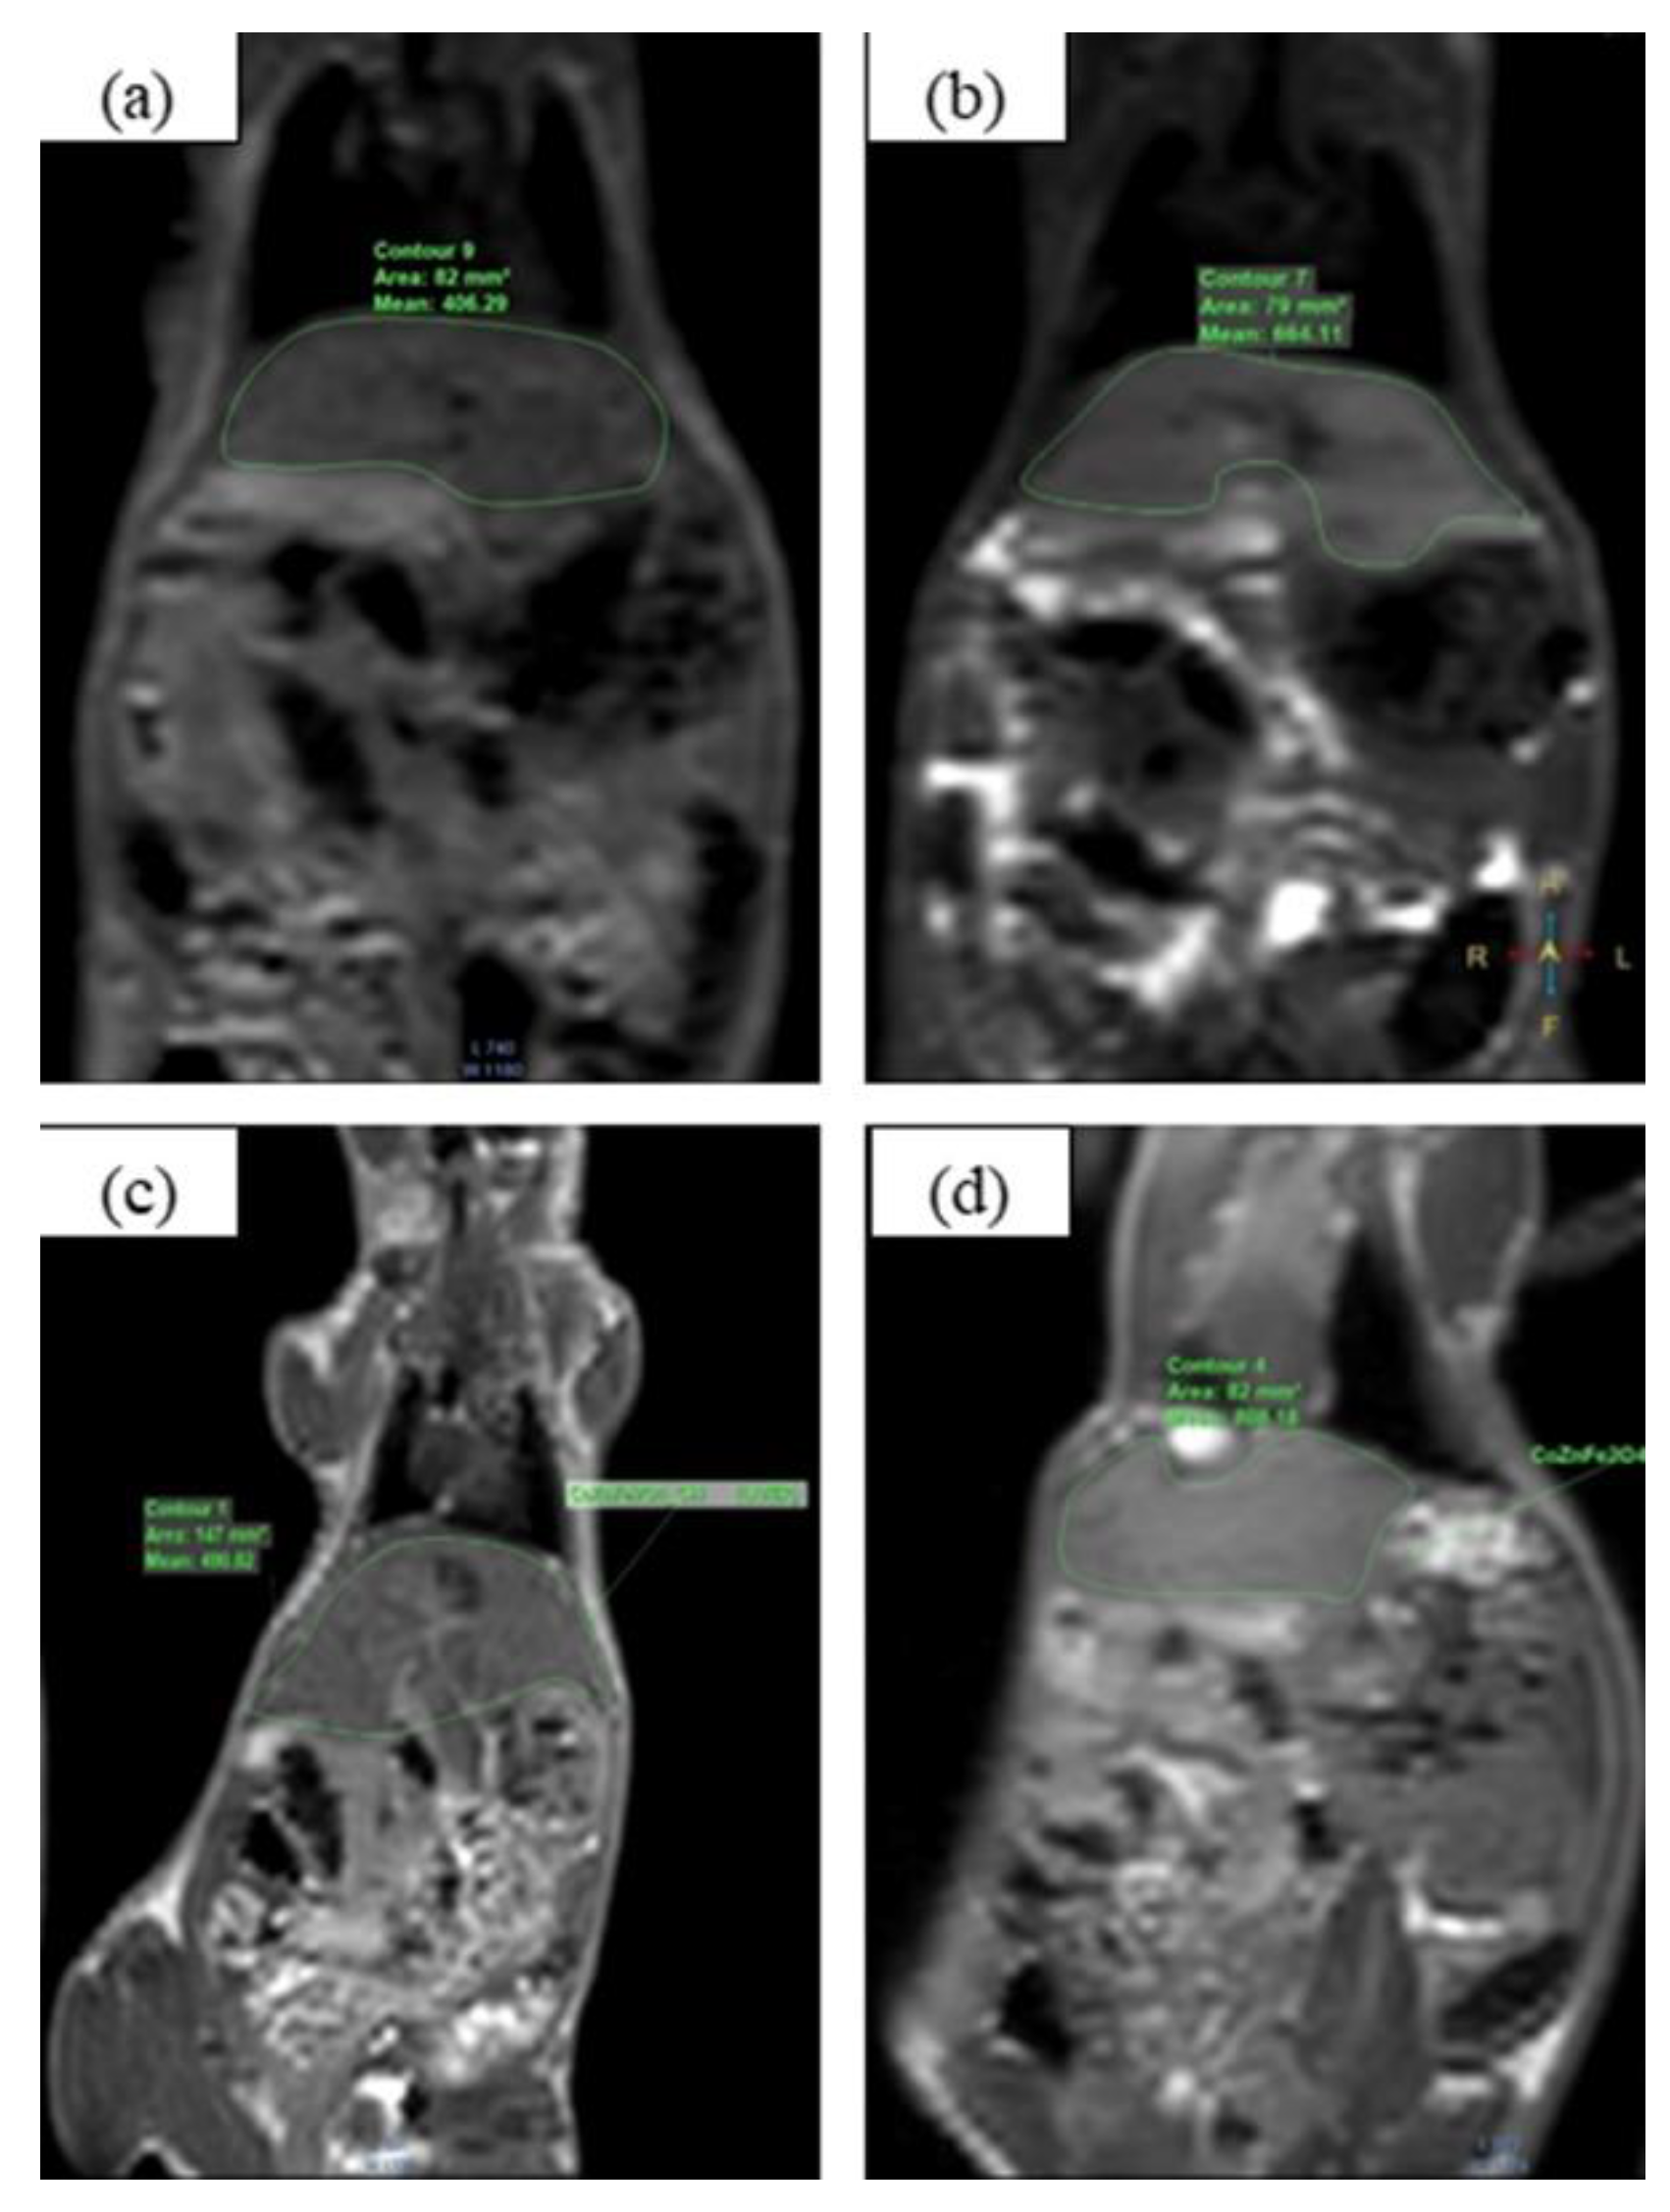

3.3. MRI Application